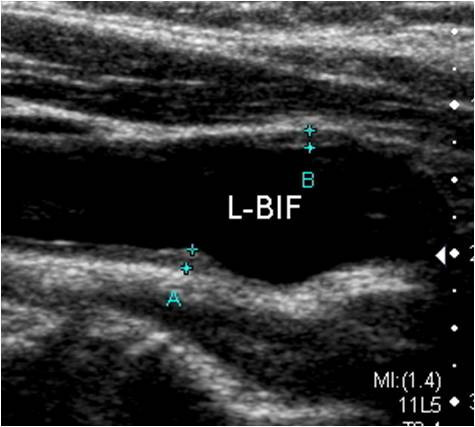

- 플라크 정의: 만하임 합의(Mannheim consensus)에 따르면, 플라크는 주변 IMT 대비 0.5mm 이상 혹은 50% 이상 돌출하거나, 절대 두께가 1.5mm 이상인 국소 비후를 말합니다. 이는 단순한 벽 비후(IMT 증가)와 구분되는 병적 병변입니다.

5) 내중막두께(IMT)와 전신 위험도

IMT 증가는 연령·성별과 무관하게 향후 심근경색·뇌졸중·심혈관 사망과 독립적으로 연관됩니다. 임상에서는 IMT≥0.9mm를 ‘아증상 장기손상’으로 간주하는 지침이 널리 쓰이며, 1.5mm 이상이면 플라크로 분류합니다. 다만 IMT는 보조 지표로 활용하며 전체 위험요인과 함께 판단해야 합니다.

2) 경동맥 협착증의 정량 평가

초음파 도플러로 최대수축기속도(PSV)와 분당 혈류를 측정해 협착을 등급화합니다. 전통적 SRU 기준에 따르면 ICA(내경동맥) PSV 125-230 cm/s는 50-69% 협착, 230 cm/s 이상이면 70% 이상 협착으로 판단합니다. 최근에는 50% 협착 문턱값을 PSV 180 cm/s로 높여 과대진단을 줄이려는 수정 기준도 확산되고 있습니다. 해석 시 플라크·내강 협소·ICA/CCA 비율 등을 종합합니다.